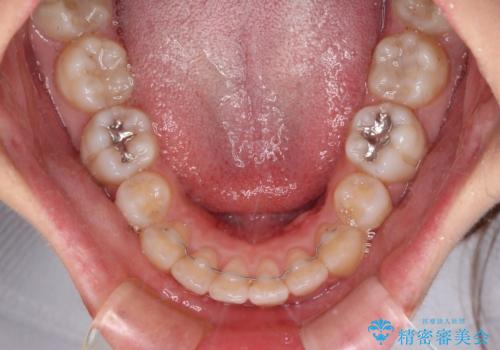

抜歯矯正の後戻り インビザライン・ライトによる矯正治療

治療途中、妊娠・出産があり、1年近く治療が停滞しましたが、無事に終了することができました。

インビザライン・ライトは提供されるマウスピースの数に制限があり、通常のタイプよりもマウスピース提供期間が短くなっている一方、安価に治療を行うことができるプランです。

治療のゴールも変更できないため、軽微な歯列不正や、後戻り改善などに適しています。